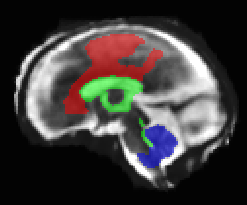

Limiting failures of machine learning systems is of paramount importance for safety-critical applications. In order to improve the robustness of machine learning systems, Distributionally Robust Optimization (DRO) has been proposed as a generalization of Empirical Risk Minimization (ERM). However, its use in deep learning has been severely restricted due to the relative inefficiency of the optimizers available for DRO in comparison to the wide-spread variants of Stochastic Gradient Descent (SGD) optimizers for ERM. We propose SGD with hardness weighted sampling, a principled and efficient optimization method for DRO in machine learning that is particularly suited in the context of deep learning. Similar to a hard example mining strategy in practice, the proposed algorithm is straightforward to implement and computationally as efficient as SGD-based optimizers used for deep learning, requiring minimal overhead computation. In contrast to typical ad hoc hard mining approaches, we prove the convergence of our DRO algorithm for over-parameterized deep learning networks with ReLU activation and a finite number of layers and parameters. Our experiments on fetal brain 3D MRI segmentation and brain tumor segmentation in MRI demonstrate the feasibility and the usefulness of our approach. Using our hardness weighted sampling for training a state-of-the-art deep learning pipeline leads to improved robustness to anatomical variabilities in automatic fetal brain 3D MRI segmentation using deep learning and to improved robustness to the image protocol variations in brain tumor segmentation. Our code is available at https://github.com/LucasFidon/HardnessWeightedSampler.